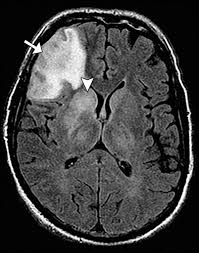

The changes spare the basal ganglia, a feature which is helpful in distinguishing an mca infarct with hemorrhagic transformation from herpes simplex encephalitis, the diagnosis in this case. Hse may result from primary infection or reactivation from latency, and it frequently involves frontal or temporal lobes, as well as the brain stem. Herpes simplex (hsv) encephalitis is the most common cause of fatal sporadic fulminant necrotizing viral encephalitis and has characteristic imaging findings. It is usually bilateral but asymmetrical. The differential diagnoses include limbic encephalitis (paraneoplastic), gliomatosis cerebri, and status epilepticus. Two subtypes are recognized which differ in demographics, virus, and pattern of involvement. Given the history of fever and seizures coupled with the mri findings of bilateral mesial temporal lobe changes, herpes encephalitis requires clinical consideration. Spinal hydatid disease is an uncommon manifestation of hydatid disease, caused by the larval stage of echinococcus granulosus, or less commonly e. Multilocularis.the larval stage is the cause of hydatid disease in humans 1. The differential diagnoses include limbic encephalitis (paraneoplastic), gliomatosis cerebri, and status epilepticus. Herpes simplex encephalitis (hse) is the most common form of viral sporadic encephalitis and, when left untreated, has a mortality rate of 70% (3, 22). This patient went on to have hsv encephalitis proven on csf pcr. Bilateral temporal lobe t2 hyperintensity refers to hyperintense signal involving the temporal lobes on t2 weighted and flair imaging.

The differential diagnoses include limbic encephalitis (paraneoplastic), gliomatosis cerebri, and status epilepticus. Ventriculitides) refers to inflammation, usually due to infection, of the ependymal lining of the cerebral ventricles. For a general discussion, and for links to other system specific manifestations, please refer to the article on coccidioidomycosis. Herpes simplex (hsv) encephalitis is the most common cause of fatal sporadic fulminant necrotising viral encephalitis and has characteristic imaging findings. Bilateral temporal lobe t2 hyperintensity refers to hyperintense signal involving the temporal lobes on t2 weighted and flair imaging. For a general discussion, and for links to other system specific manifestations, please refer to the article on hydatid disease. Given the history of fever and seizures coupled with the mri findings of bilateral mesial temporal lobe changes, herpes encephalitis requires clinical consideration. It is most often due to meningitis. Multilocularis.the larval stage is the cause of hydatid disease in humans 1. Spinal hydatid disease is an uncommon manifestation of hydatid disease, caused by the larval stage of echinococcus granulosus, or less commonly e. Terminology cerebritis is essentially the same as encephalitis except that it is used to denote brain par. It is a common finding on brain mri and a wide range of differentials should be considered 1. It is usually bilateral but asymmetrical.

Two subtypes are recognised which differ in demographics, virus, and pattern of involvement. Mri demonstrates extensive edema in the right temporal lobe with areas of intrinsic high t1 signal, in keeping with hemorrhage. Terminology the entity or closely related variants have also been. Coccidioidal meningitis refers to central nervous system involvement of the dimorphic fungus coccidioides spp, mainly coccidioides immitis and coccidioides posadasi. Note the high signal in the caudate heads and putamen on flair.